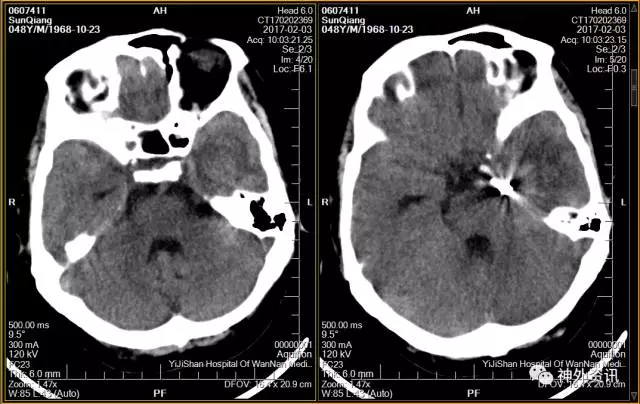

头颅CT示:蛛网膜下腔出血,脑干旁30mm*16mm占位,怀疑颅内动脉瘤可能。

脑动脉CTA示:左侧颞叶血肿,烟雾病伴血流相关性动脉瘤。

(头颅CT示:蛛网膜下腔出血,左侧颞叶血肿)

(增强CT:环池周围凌乱血管影伴瘤样扩张)